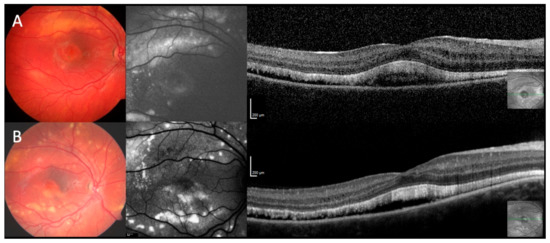

2.2. Clinical Findings

2.3. Clinical Phenotypes

2.4. Fundus Autofluorescence

2.5. Optical Coherence Tomography